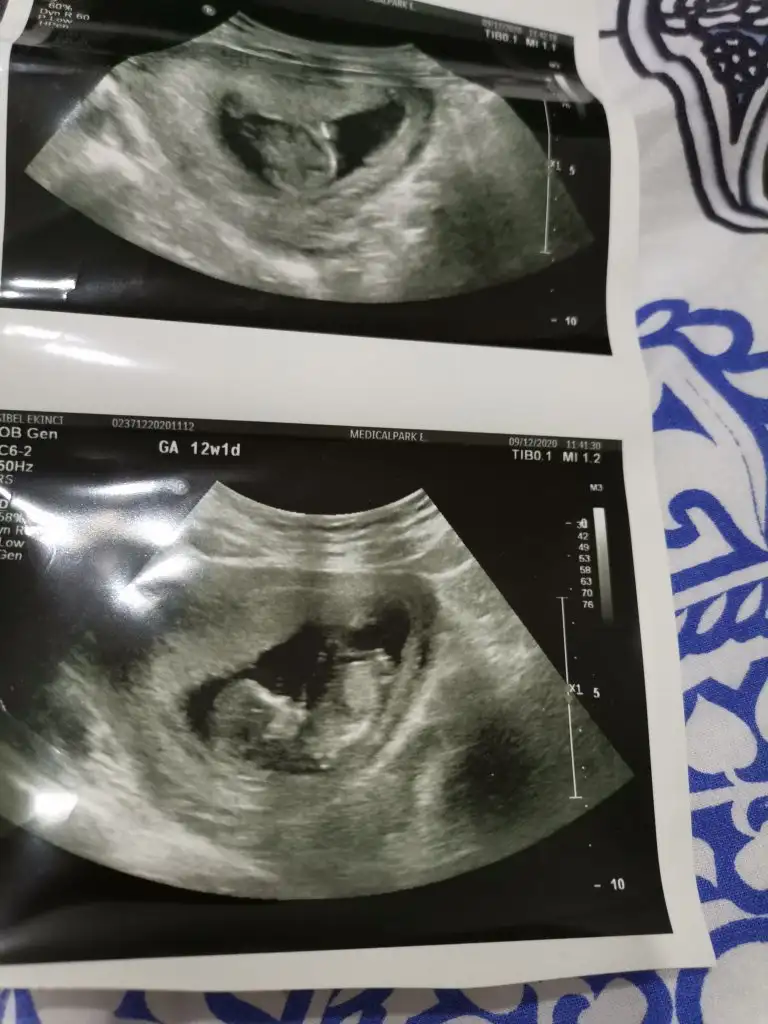

Benim içinde bir yorum yapar mısınız

• IMG_20201209_163424.webp

IMG_20201209_163424.webp

48,3 KB · Görüntüleme: 66